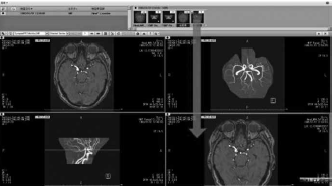

MRA検査の別シリーズとして、EIRL aneurysmの解析結果が表示される(青矢印)。

(MRA=MR angiography)

EIRL aneurysmはAI技術を活用し、頭部MR angiography(以下、MRA)画像から未破裂脳動脈瘤と同様の特徴を持つ領域を自動で検出し、その位置を読影者に提示するソフトウェアである(図1)。コンピュータ支援診断computer-aided diagnosis:CAD)の中でも、病変検出を得意とする代物だ。MRA画像がPACSサーバーに取り込まれてから、EIRL aneurysmによる解析が始まり、5分程度で同じ検査の別シリーズとして解析結果が表示される。具体的には、直径2mm以上の脳動脈瘤に類似した候補点を検出し、脳動脈瘤の可能性が高い順番に最大5つの候補点を表示する(図2)。頭部MRA水平断元画像の解析結果の表示画面には、候補点の総数が明示され、丸で囲われた各々の候補点には数字が振られる。たとえば、“1” と番号付けされた候補点は、CADが最も脳動脈瘤らしいと判断した箇所だ。頭部MRAのmaximum intensity projection(以下、MIP)画像にも解析結果を載せることができ、Axial表示かMIP表示、あるいは両方の表示にするかはシステム設定より選択できる。

直径2mm以上の脳動脈瘤に類似した候補点を検出し、脳動脈瘤の可能性が高い順番に最大5つの候補点を表示する。

Axial表示(左)、MIP表示(右)のどちらにも対応可能であり、システム設定により選択できる。

(MIP=maximum intensity projection)